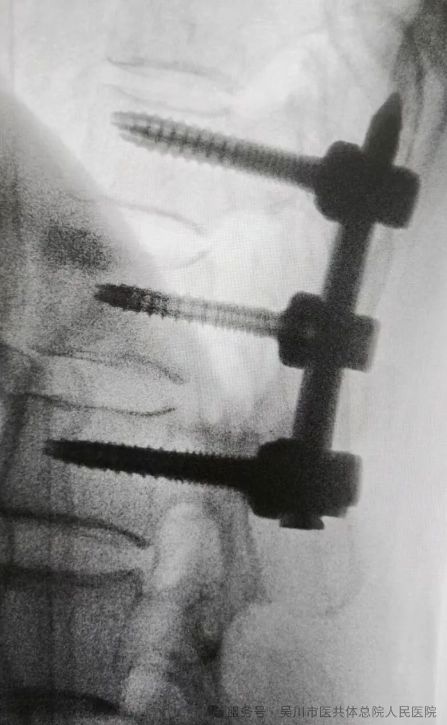

70岁的文先生被反复腰背部疼痛伴右下肢麻痛困扰1年,近期症状突然加重,严重影响生活质量,于是选择到我院骨外科三区治疗。经保守治疗效果不佳,MRI检查显示其腰4、5椎间盘向后脱出,双侧神经根及马尾受压,椎管显著狭窄,病情危急。

该科主任、主任医师曾维带领骨外科三区团队仔细研判病情,决定自主开展高难度手术。术中,医护团队精准实施 “腰椎后路椎板切除 L4、5椎管减压+ L4/5椎间盘切除椎间融合 + 腰4、5椎体椎弓根钉内固定术”,手术全程顺利。术后,文先生下肢麻痛等症状明显减轻,久违的轻松感让他对曾维团队的精湛医技赞不绝口。